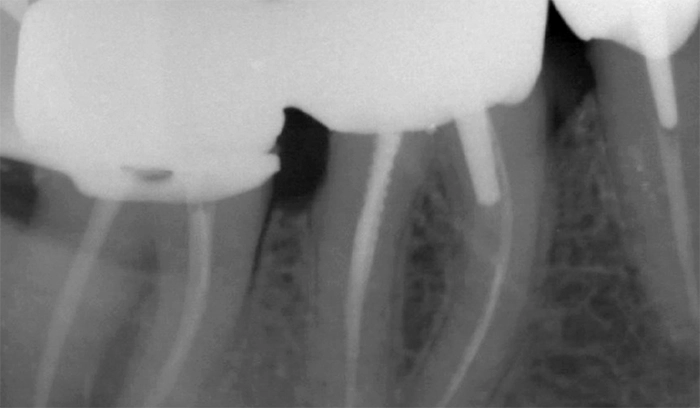

Dentisterie restauratrice

- Élément de liste #1

- Élément de liste #1

- Élément de liste #1

- Élément de liste #1